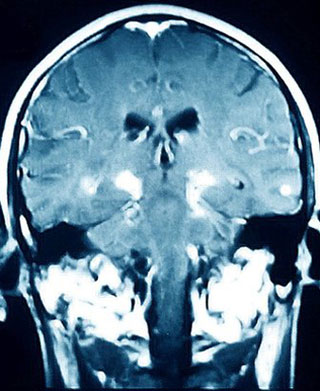

Các thử nghiệm hiện đang tuyển dụng trực tuyến nhằm tìm kiếm những người mắc và không mắc bệnh, Parkinson là một trong những bệnh thoái hóa thần kinh phổ biến nhất, ảnh hưởng tới khoảng 127.000 người ở Anh.Việc chẩn đoán dựa trên các triệu chứng bao gồm run, cứng cơ và khó khăn khi di chuyển và nói năng. Tuy nhiên các nghiên cứu đã cho thấy có tới 20% người được chẩn đoán mắc bệnh Parkinson không biểu hiện các dấu hiệu của bệnh khi khám nghiệm tử thi. TS. Max Little, một nhà nghiên cứu toán học cùng với nhóm nghiên cứu sự phức tạp và phi tuyến tính của Đại học Aston giải thích: “Phần lớn những người mắc bệnh này sẽ không bao giờ được đánh giá một cách khách quan”. Nhóm nghiên cứu của TS. Little đã phát triển phần mềm sử dụng micro và bộ cảm biến chuyển động của một chiếc điện thoại thông minh thông thường để cung cấp dữ liệu bổ sung cho việc đánh giá lâm sàng truyền thống.

| Parkinson là một trong những bệnh thoái hóa thần kinh phổ biến nhất. |